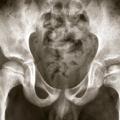

Ostéochondrite de hanche gauche

OSTEOCHONDRITE